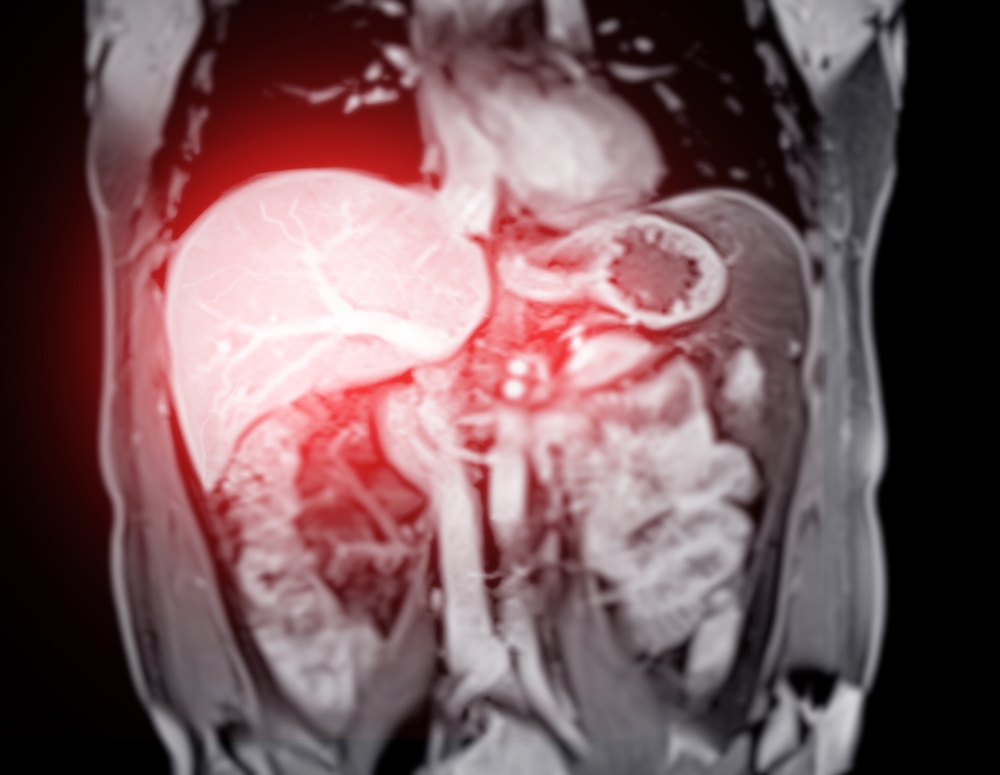

Rezonanța magnetică (RMN) hepatică

RMN-ul este metoda de elecție pentru evaluarea depozitelor de fier la nivel hepatic. Acest test este neinvaziv și poate determina severitatea încărcării fără a fi nevoie de biopsie. Rezultatele sunt exprimate în unități R2 sau R2*, care se corelează direct cu concentrația de fier în țesut.